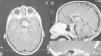

En el estudio se realiza RM cerebral, en la que se observa lesión sólida centrada en la región selar con extensión supraselar (fig. 1). A continuación se realiza tomografía computarizada (TC) con reconstrucción tridimensional: sospecha de osteocondroma selar con extensión supraselar e invasión del seno cavernoso izquierdo (fig. 2).